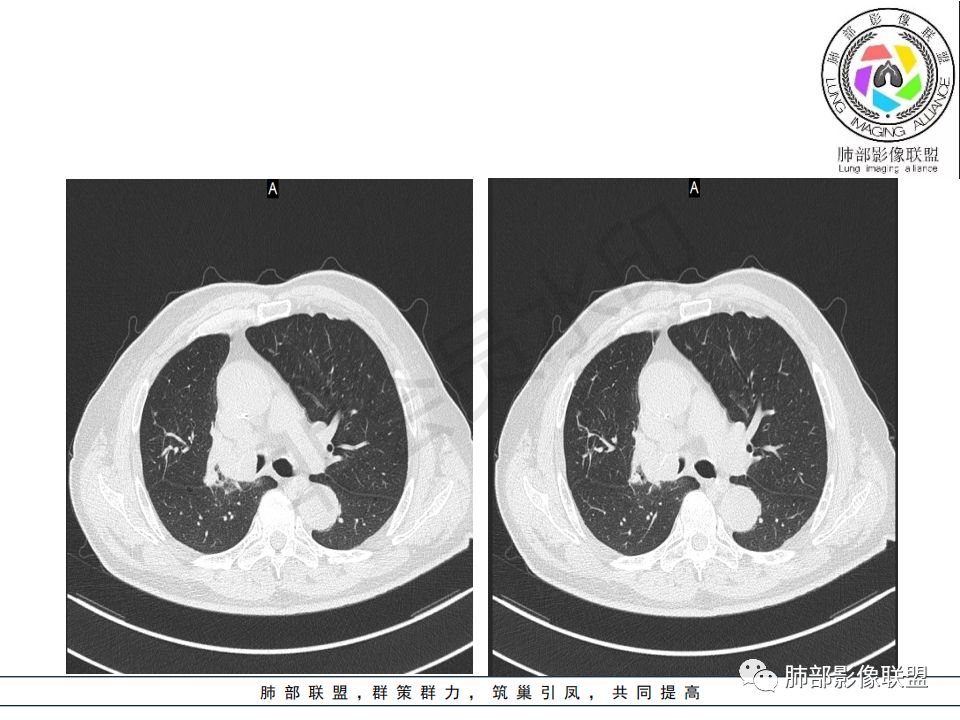

老年男性,右肺上叶尖段支气管截断,右肺尖段肺不张,病灶内见细沙粒样钙化,附近见多发结节影,一元论,考虑鳞癌并肺内转移。

右肺主支气管内外软组织影,支气管变窄截断,右肺上叶成软组织密度,其内见细沙样钙化,周围看见小结节,右肺门看见一淋巴结稍大,增强不均匀强化,胃癌病史,考虑:转移,或原发肺恶性鳞癌。

老年男性,右肺气管内软组织影,支气管变窄截断,右肺上叶阻塞性肺不张,内见细点状钙化,周围看见小结节,增强不均匀强化,考虑:原发肺恶性鳞癌。胃癌病史,转移不出外。鉴别神经内分泌癌,类癌。

晨读病例:老年男性,症状轻,右侧胸廓略塌陷,右肺主支气管内外软组织影,支气管变窄截断,右肺上叶不张,其内见细砂样钙化,周围看见小结节,右肺门看见一淋巴结稍大,增强不均匀强化,胃癌病史,常规考虑:转移,或原发肺恶性鳞癌。鉴别支气管TB?